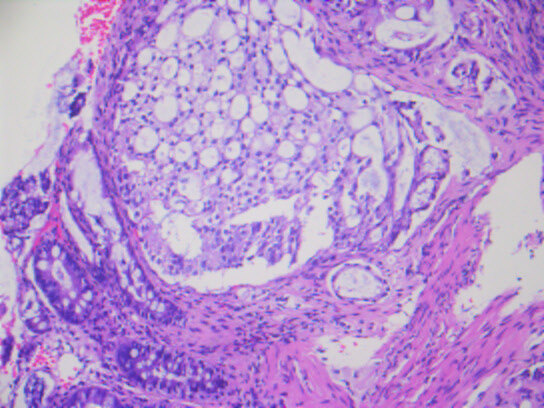

几天前,入我院行肠镜检查,并活检,显微镜下可见癌浸润于直肠粘膜之间。

最终,我们以上述HE形态为线索,老年男性,直肠占位,为XY坐标,我们初步音箱诊断就是前列腺腺泡腺癌浸润至前列腺腺外,累及直肠并形成肿块,浸润直肠全层至粘膜内。

上述免疫组化结果辅助诊断为前列腺腺泡腺癌累及直肠。